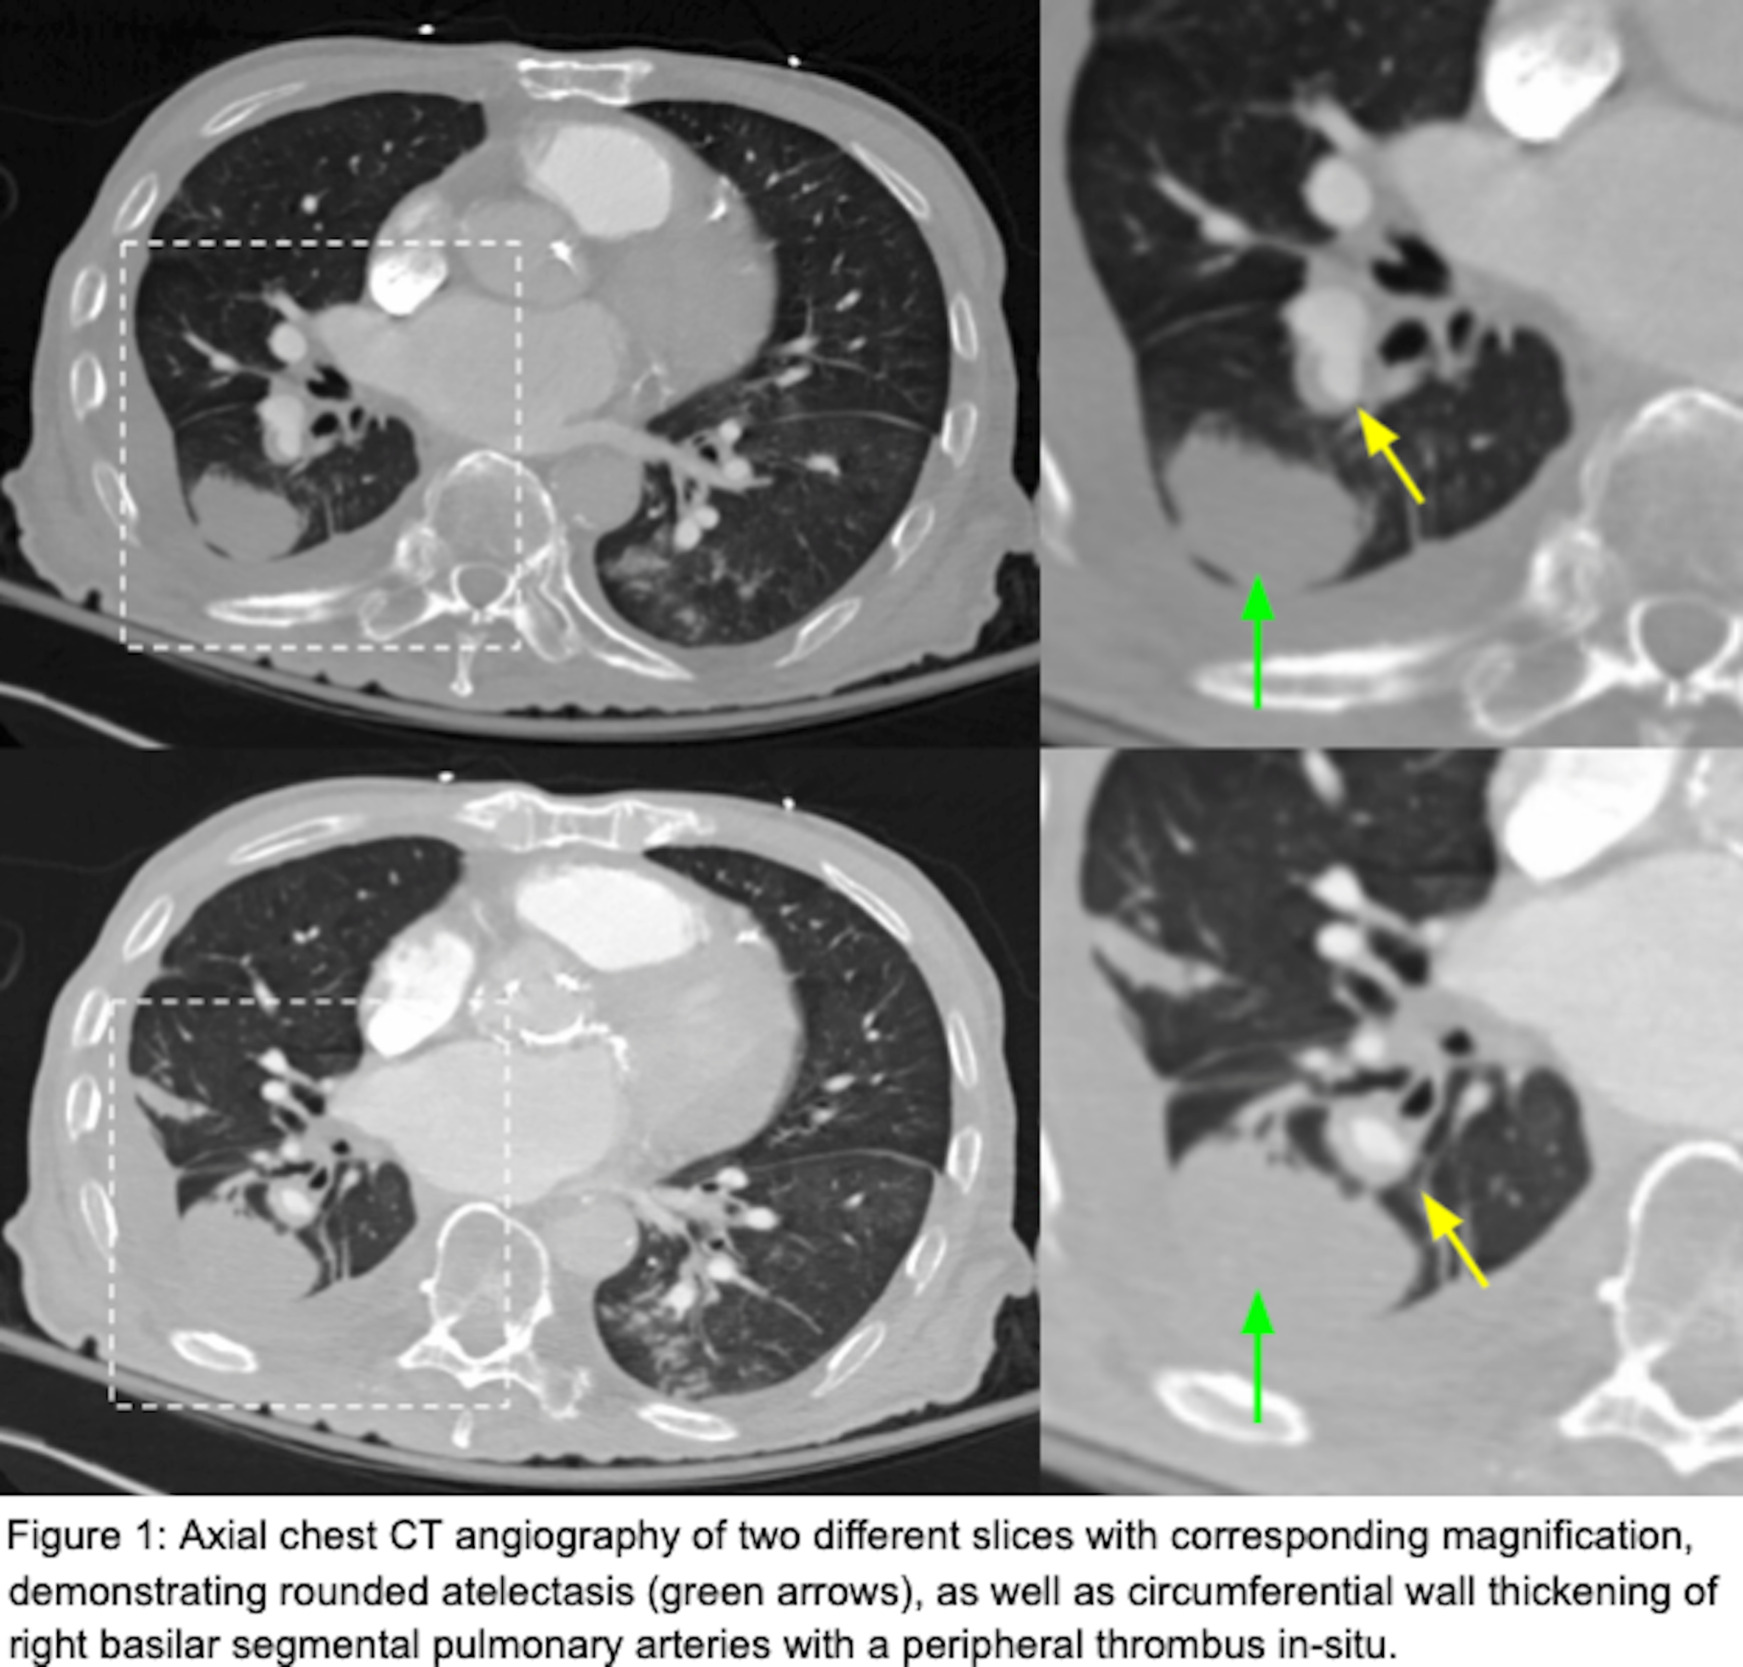

He had a chest radiograph on admission demonstrating patchy bibasilar opacities, with small bilateral pleural effusions which were greater on the right. Chest computed tomography angiography (CTA ) demonstrated a small chronic loculated right-sided pleural effusion with pleural thickening and pleural calcifications. Adjacent to this pleural effusion, there was a round opacity with evidence of volume loss and a comet tail sign compatible with rounded atelectasis. There was also demonstration of circumferential wall thickening of right basilar segmental and subsegmental pulmonary arteries with a peripheral thrombus within both of these pulmonary arteries extending to the rounded atelectasis (Figures 1 and 2). This was favored to represent an in-situ thrombus over a pulmonary embolism. Additional findings were concerning multifocal pneumonia versus aspiration, a second area of rounded atelectasis in the right middle lobe, subpleural reticular opacities, cardiomegaly, mediastinal and hilar adenopathy, and a small left pleural effusion. His CT imaging was then followed by a bilateral lower extremity venous duplex ultrasound, which was negative for evidence of deep venous thrombosis (DVT). A formal echocardiogram revealed a moderately dilated left ventricle with an ejection fraction of 15%, moderately dilated right ventricle with severely reduced systolic function, moderate-to-severe mitral regurgitation and normal pulmonary pressures. Imaging from one year prior to this admission demonstrated unchanged right lower lobe rounded atelectasis with no radiographic evidence of a thrombus in this area, although this is of limited interpretation due to the type of study performed. A previous echocardiogram from one-year prior revealed mitral regurgitation, and a globally hypokinetic left ventricle with an ejection fraction of 20-25%.

This case report identifies a patient with right-sided rounded atelectasis with in-situ thrombus in the supplying segmental and subsegmental arteries, a rare radiological finding. Both the rounded atelectasis and in-situ thrombus likely did not contribute to this patient’s acute respiratory decline, as the rounded atelectasis was demonstrated to be unchanged over a one-year interval; further, the thrombus was located in the periphery in segmental/subsegmental arteries supplying the rounded atelectasis, an area which was contributing to anatomical dead space. Additionally, image-based signs suggestive of an acute pulmonary embolism were not observed. These include pulmonary artery dilation proximal to the thrombus and a central filling defect with acute angles within vessel walls.3 Moreover, signs suggestive of a significant pulmonary embolism causing tricuspid regurgitation, or retrograde contrast flow into the inferior vena cava were not observed. On the contrary, we did observe pulmonary artery wall thickening without proximal dilation and a filling defect with obtuse angles surrounding the thrombus, which suggests this was not an acute thrombus but rather chronic. Collectively, these findings represent chronic changes and are interesting radiological findings. The association between rounded atelectasis and in-situ thrombus has not been previously described in a recent review2 or found elsewhere in the literature.